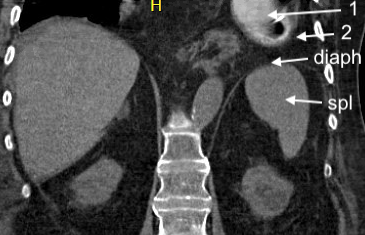

What are structures labeled 1 and 2 (same structures in both images)?

Spleen and diaphragm are difficult to see in this still image, so those are labeled

What are structures labeled 1 and 2?

With CT scan, we see that

-structure #1 is the stomach (with NG tube)

-structure #2 is soft tissue

Answers to above questions - CXR and POCUS labeled here

This is due to a hiatal hernia, with upper portion of the stomach passing above the diaphragm and into the thorax.